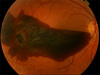

HYPHEMA